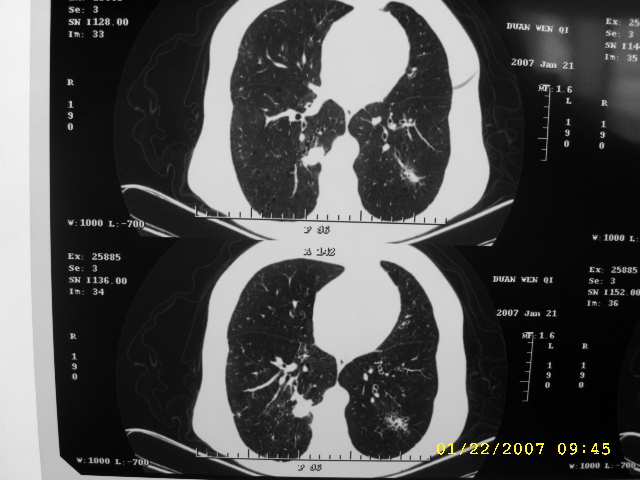

女,75.胸痛。

07.01.21.

明显的不规则形肿块,分叶、短毛刺、胸膜刺激征,血管扭曲征等周围型肺癌的征象明显,应首先考虑周围型肺癌。应与肺多发结核球相鉴别

双侧肺内块状病灶,均见分叶毛刺,左肺见典型胸膜凹陷,双侧双原发癌.

1.双肺上叶及右肺下叶结节,周围散在卫星灶,接近4年的病史,纵隔无肿大淋巴结,考虑结核

2.桶状胸,慢支,肺气肿